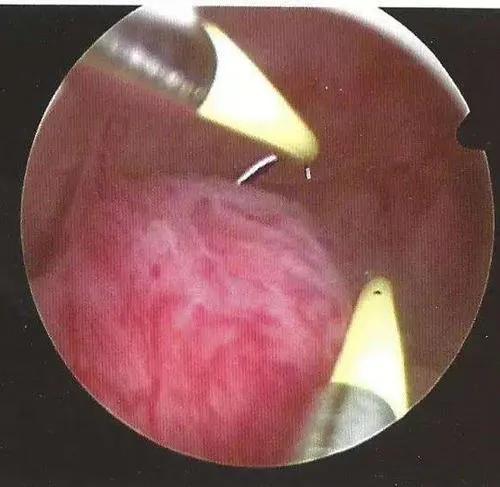

宫腔黏连